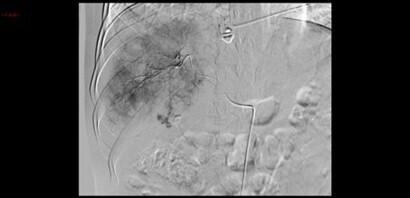

Le traitement suivant est par la suite réalisé.

Question 12 - À quoi correspond ce traitement (une ou plusieurs réponses exactes) ?

L’embolisation vasculaire radioguidée (artériographie) est la technique privilégiée pour le traitement des hémorragies abdominales en urgence. Elle consiste, après ponction artérielle, à la cathétérisation du vaisseau responsable du saignement, le plus sélectivement possible, et l’injection de matériel embolisateur.

La première figure montre bien la flaque artérielle du produit de contraste (saignement actif artériel) au niveau du segment V.

La seconde figure, elle, correspond au contrôle en fin de procédure après embolisation de la branche artérielle hépatique responsable du saignement, montre la disparition de cette flaque.